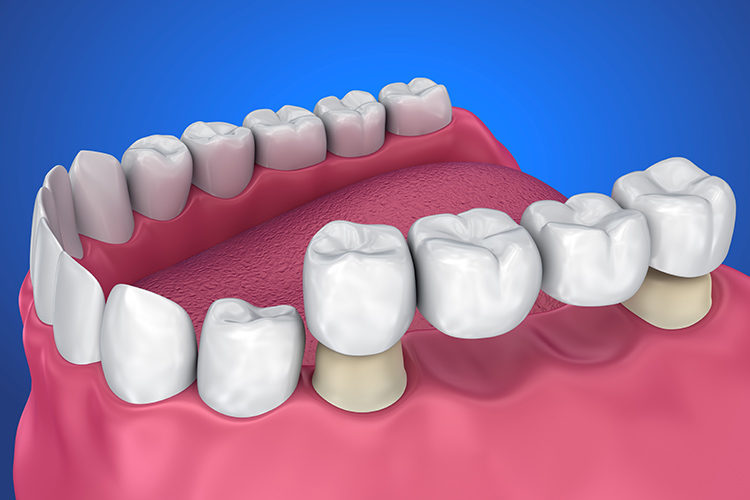

クラウン

クラウンは、自分の歯を削り、それを土台にして人工の歯を被せる治療のことです。保険治療の金属製素材の他、保険外治療ではセラミックのご用意もございます。セラミックは、金属アレルギーの心配もなく、見た目の影響も少ないです。

ジルコニアセラミックとは、オールセラミックの審美性と金属の強度を併せもった、素材です。金属を一切使用していないので、光の透過性もよく、金属アレルギーや歯ぐきの変色の心配もありません。強度が優れているため、今までオールセラミックスではできなかったブリッジでの使用も可能です。

メタルボンドとは金属のまわりにセラミックを貼り付けた被せ物です。中身が金属で出来ているので、強度がオールセラミックより強く、表面がセラミックでできているので、自然な色合いで審美性にも優れていますが、歯ぐきの変色や金属アレルギーが起こる可能性などのデメリットがあります。治療箇所により、比較的強度が必要な個所の治療やブリッジに適しています。